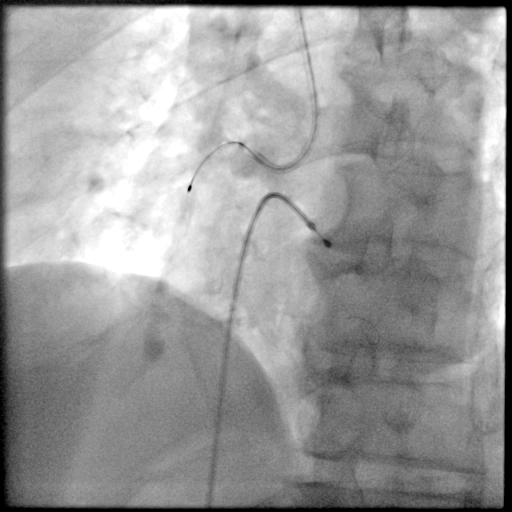

PCI过程-球囊PTCA

预置临时起搏器后,7F AL1.0无法到位,更换为7F SAL1.0至RCA开口,应用非顺应性球囊2.5X15mm,于RCA中段病变处以12-18atm扩张,球囊膨胀不佳。